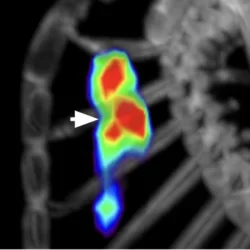

In Vivo Molecular Imaging of Cardiovascular Calcification

We have demonstrated that 18F-NaF positron emission tomographic (PET) labels cardiovascular calcification (arrow) in mice. Fluoride ions adsorb onto surfaces of hydroxyapatite, replacing the hydroxyl groups, to form fluoroapatite. Microarchitectural changes of cardiovascular calcification are affected in response to interventions, such as exercise, aging, and lipid-lowering drugs.